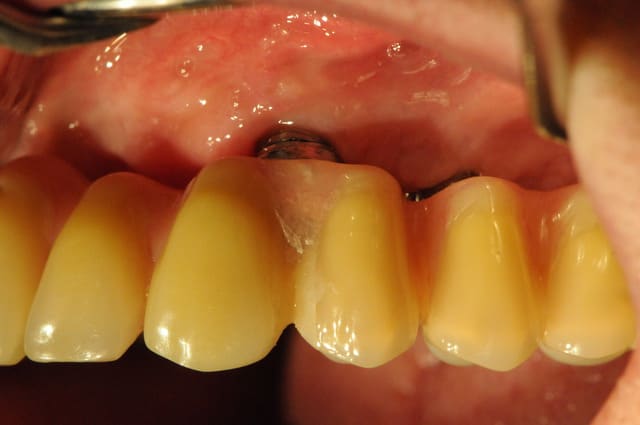

pas pris le temps de te l'envoyer mais voici un cas d'acharnement et qui pourrait compléter la discussion de comblement ou pas et nécessité de scanner ou pas

début en 2001 : patient avec perte de 32 me demande de remplacer dent manquante réponse ok avec pano et rvg pas de scan vu la hauteur visible et en pus on est en 32 .

le jour de la pose : j'avais prévu un 12*3.3 je le mets en place mais tourne à15 newton donc poubelle et je mets en pace 4*12 blocage à 30 newton mais sensation particukière au forage

puis attente et au deserrage de la vis je dévisse sans effort ce 4*12 la nje fait 1 scan qui confirme qu'iln'y a rien dans le "sandwich" bicortical qui est bien présent donc endo de 33 depose en deserrant la vis de l'implant sans effort curetage ++++ pas de prf et perlimpinpin attente de cicat 6 mois

et repose d'1 3.3*12 (on en est à 3 futs) attente bonne sensation au forage et attente avec atelle collée toujours puis 6 mois après en serrant le fm

à 30 le patient me dit "il y à qqchose de sensible" je mets la provisoire quand même qui est restée en place 1 an et demi mais je l'ai déposé (mobilité +++) et ai réalisé une prothèse "conventionelle"